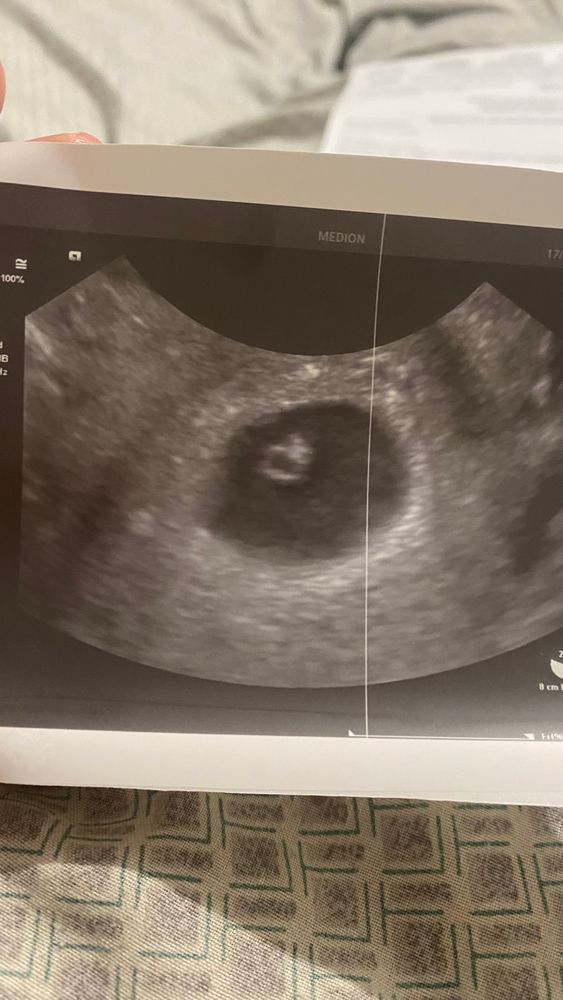

Узи 6+3. На память,слезы счастья🥹

Какое фото красивое 😍😍😍 яичко большое с эмбриончиком❤️ Рада за тебя очень, ты заслуживаешь на здоровую и легкую беременность🙏🏻